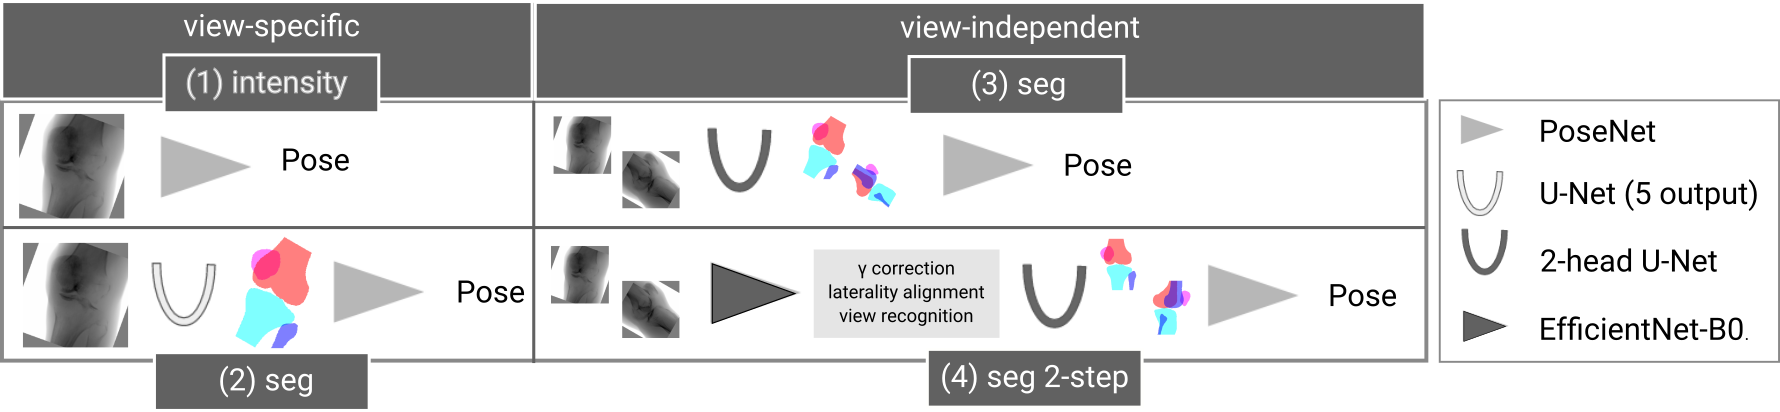

An overview of the complete framework for fully automated C-arm positioning towards desired standard views during knee surgeries is given in Fig. 1. The anterior-posterior (a.-p.) and the lateral standard view showed to be sufficient for various diagnostic entities [3].

2.2 Shape-based positioning framework:

The proposed shape-based positioning framework was trained jointly for both standard views (Fig. 1). It consists of two modules: The first is responsible for a view classification, in-plane rotation and laterality alignment, directly estimated from the image intensities. Thereby, pose ambiguities and data variation are addressed, simplifying the task for the subsequent module to estimate the optimal C-arm positioning for the desired standard view, employing shape features.

(1) Intensity-based multi-task classification and regression module: For simultaneous in-plane rotation regression, view recognition, and laterality classification, an EfficientNet-B0 feature extractor [18, 14] was extended with two binary classification heads with one output neuron, followed by sigmoid activation, and one regression head, with the same architecture, but 2 outputs, omitting the activation. The in-plane rotation is mapped to sin/cos-space to ensure a continuous Loss function during optimization. All training examples were aligned with the same laterality during data simulation which would otherwise result in pose ambiguities. Thus, to train the laterality classifier, the training examples were randomly flipped horizontally with and the corresponding label was adapted accordingly. The weights were optimized using Binary Cross Entropy Loss for the classification heads, and Mean Squared Error for the regression head.

(2) Shape-based pose regression: Following surgical characteristics for recognizing correct standard views of the knee, a view-independent shape-based pose regression framework was developed. The architecture is based on a 2D U-Net [12] with two view-specific segmentation heads, because the segmentation labels differ for both views. The extracted shape features are used as input for the pose regression network that outputs the necessary C-arm pose update (, , , ) to acquire the desired standard view [11].

In an ablation study, the proposed shape-based view-independent pose regression was compared to view-specific direct intensity-based pose regression [11]. Further, the complete pipeline (2-step) is compared to a 1-step segmentation-based approach trained view-specific and view-independent (Fig. 4). Evaluation was performed on the simulated test DRRs and cadaveric X-rays (Fig. 5).